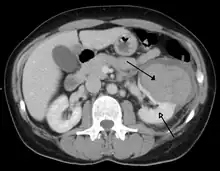

Abdominal trauma resulting in a right kidney contusion (open arrow) and blood surrounding the kidney (closed arrow) as seen on CT | |